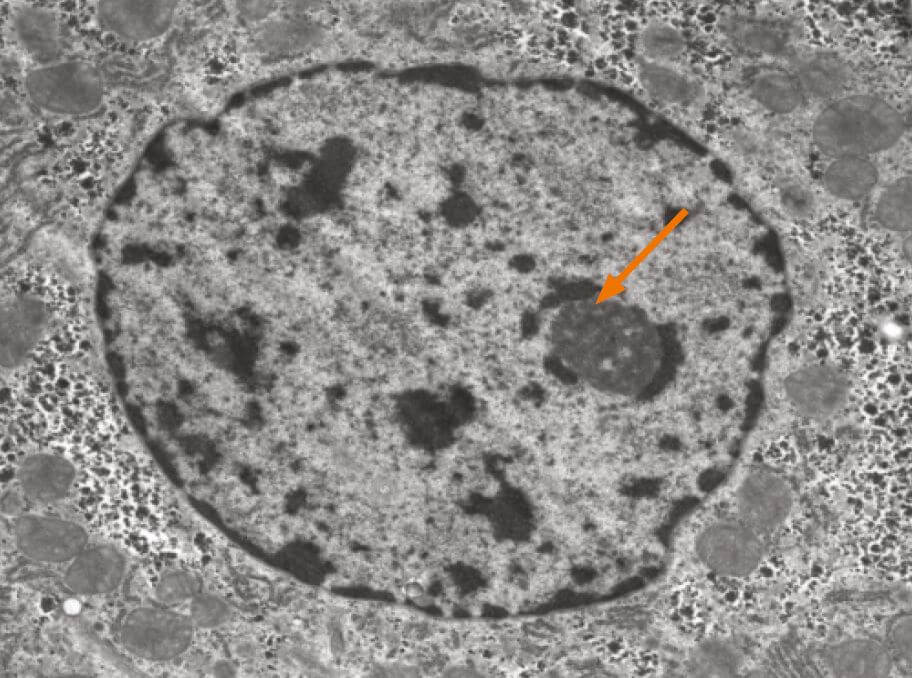

The Nucleolus

The nucleolus is the most prominent structure in a cell nucleus. It is the site of ribosomal RNA (rRNA) transcription, pre-rRNA processing and ribosome subunit assembly. The nucleolus is a dynamic structure that assembles around the clusters of rRNA gene repeats during late telophase, persists throughout interphase and then disassembles as cells enter mitosis. Alterations in both number and shape of nucleoli are linked to cancer and cancer prognosis.

The nucleolus is a ribosome factory, composed of deoxyribonucleic acid (DNA), ribonucleic acid (RNA), and protein. At the nucleolus, a long ribosomal RNA (rRNA) precursor molecule is transcribed from DNA, processed into three mature RNAs, and packaged together with specific proteins to make the large and small ribosomal subunits. Once the subunits have been assembled, they are transported out of the nucleolus to the cytoplasm for use in translation (protein synthesis). Human chromosomes contain five nucleolar organiser regions (called NORs), located on the short arms of the chromosomes 13, 14, 15, 21, and 22. In humans, each NOR contains approximately one hundred tandemly repeated rRNA gene copies. The NORs of different chromosomes typically come together in interphase. Thus, a single nucleolus is often made up of rRNA genes from two or more different NORs.

Internuclear structures do not have membranes, but the density of nucleoli makes them quite visible with most nuclear staining’s. It is, however, a challenge to obtain a proper segmentation of nuclei in light microscopical images, a requirement for quantitative measures.